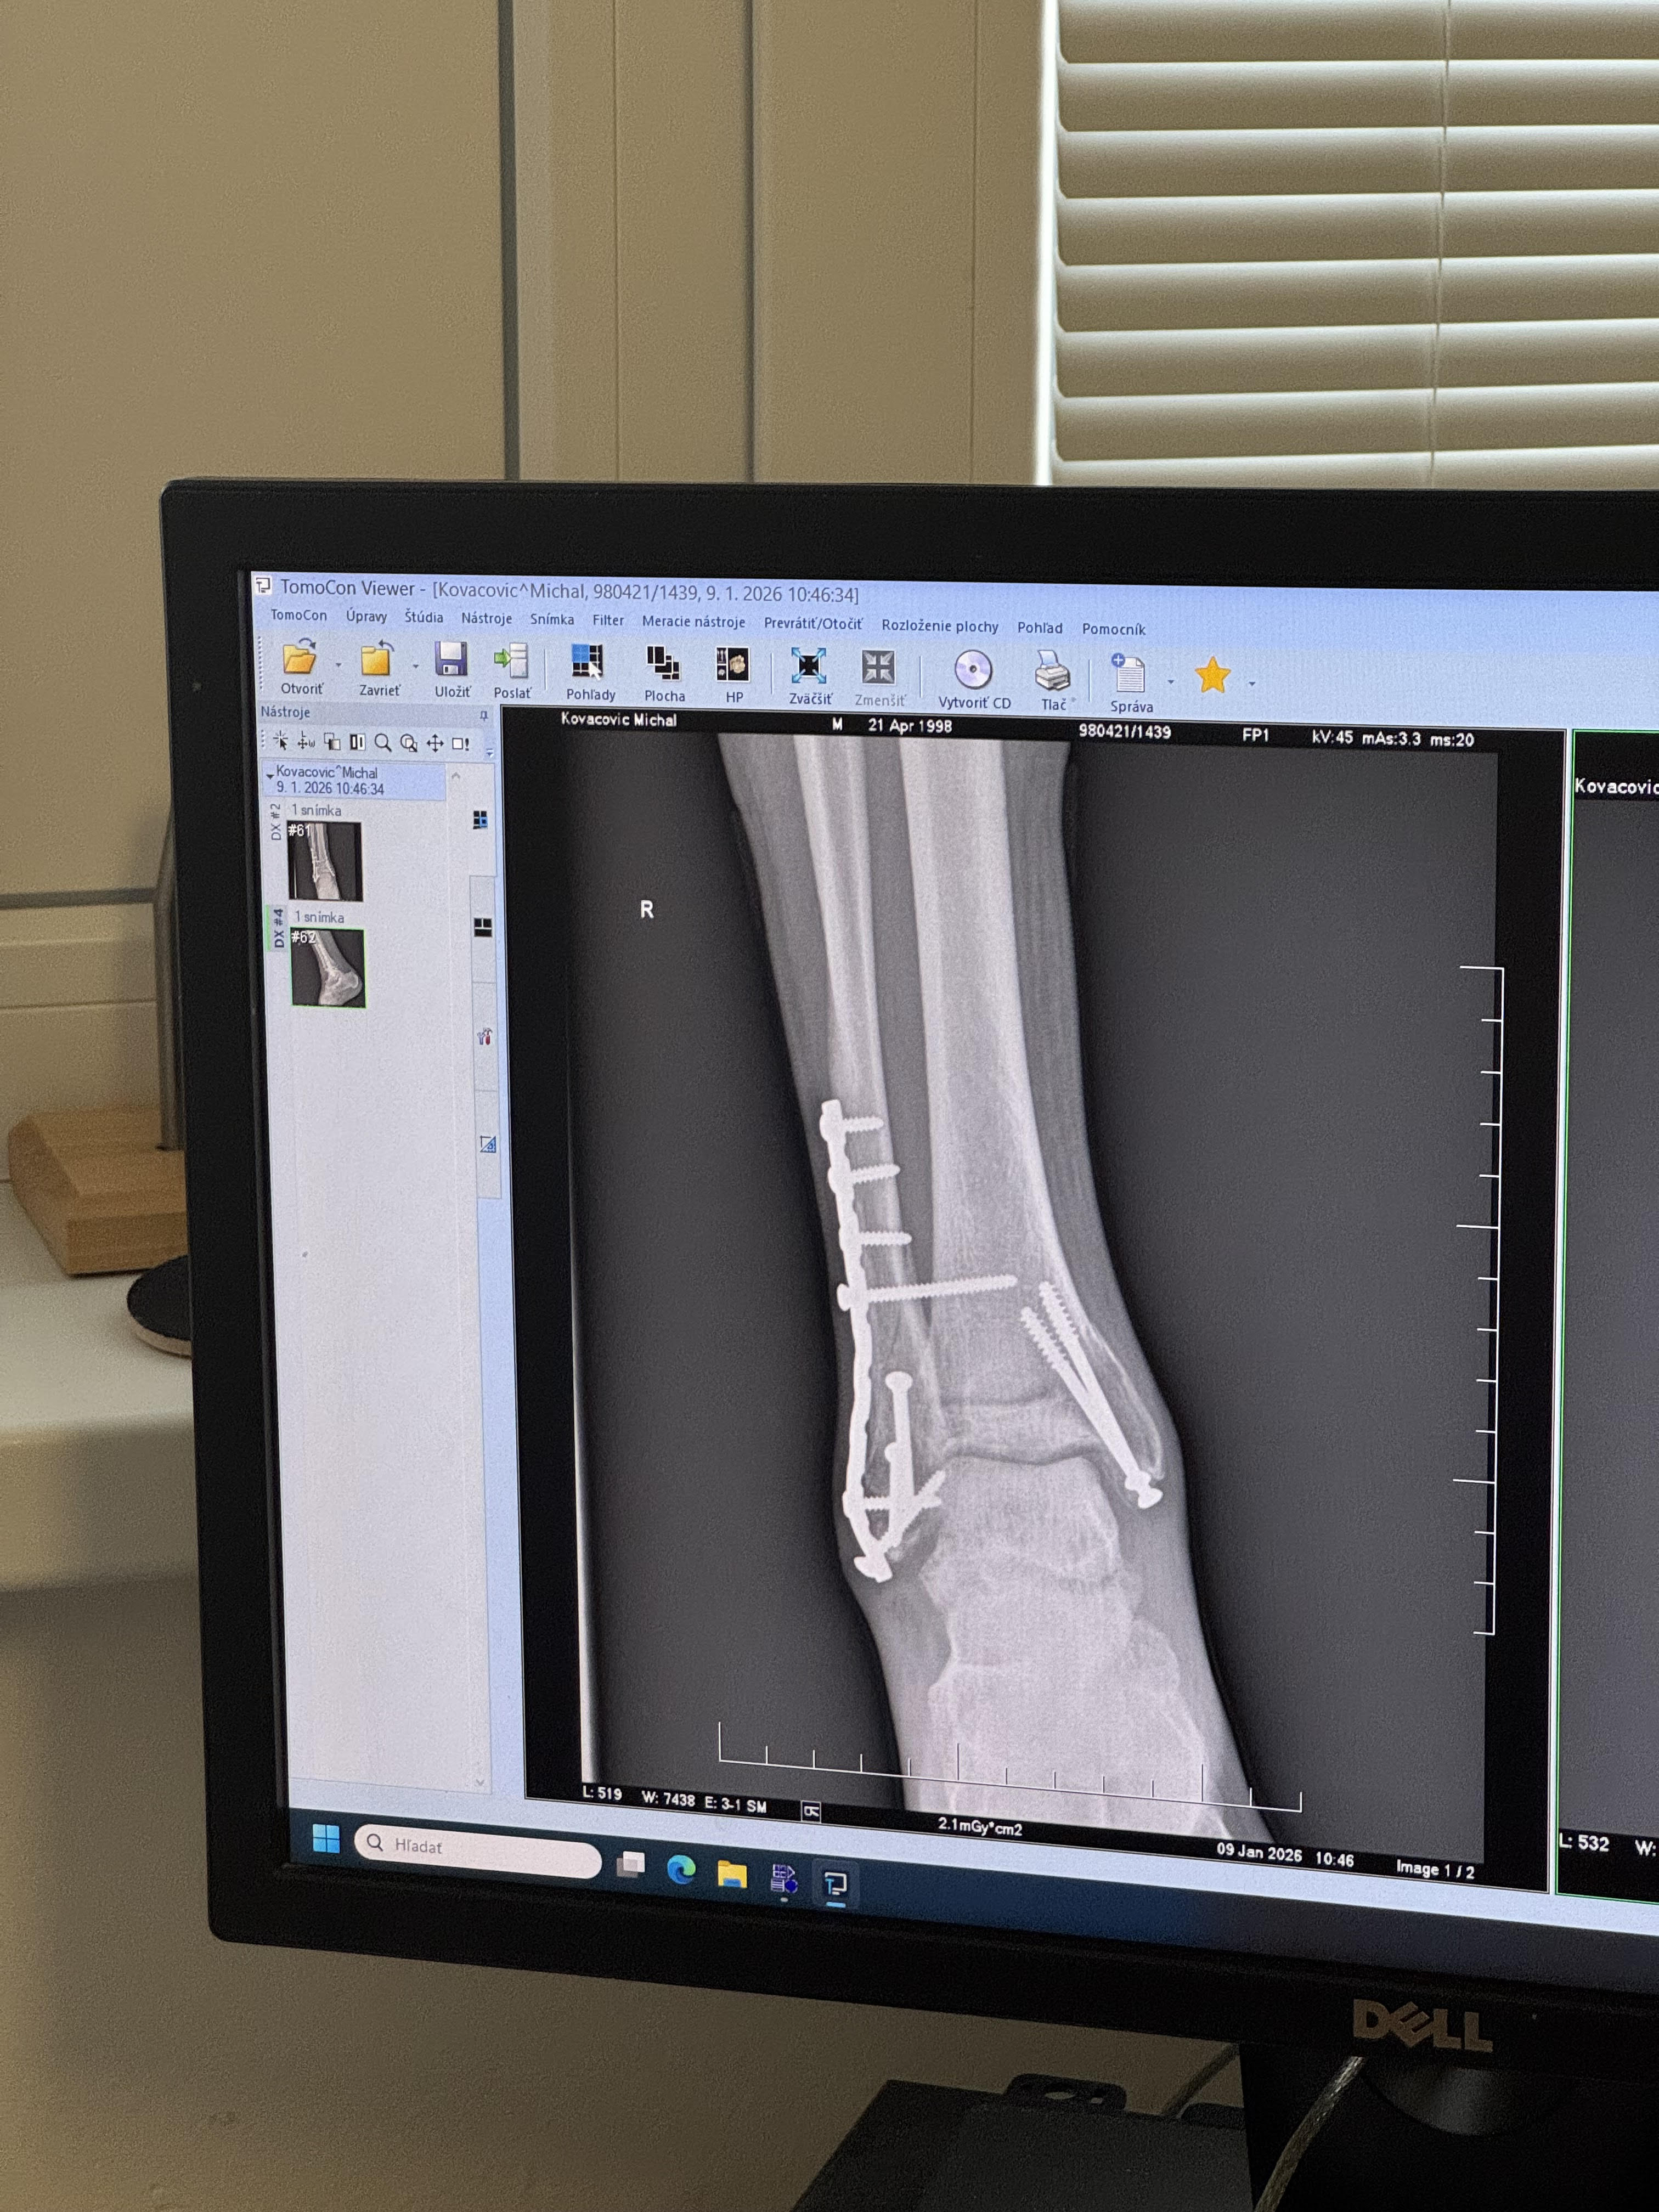

Čau čau makeris, život už docela ide po tom zimnom spánku, čo si si neplánovane doprial, hahah. Hej no, nepríjemná záležitosť, ale tak čo už, aj toto je súčasť hry, ktorú hráme. V novembri na poslednom repre tripe v Mníchove sa mi hneď prvý deň podarilo si prisadnúť nohu, čo znamenalo zlomené všetky tri kosti členku a celkom komplikovanú operáciu, ehhhh… Našťastie mám okolo seba veľa šikovných ľudí, ktorí mi pomáhajú dostať sa ešte do lepšej formy, ako som bol predtým!

Aj toto je bmx life - zlomený členok